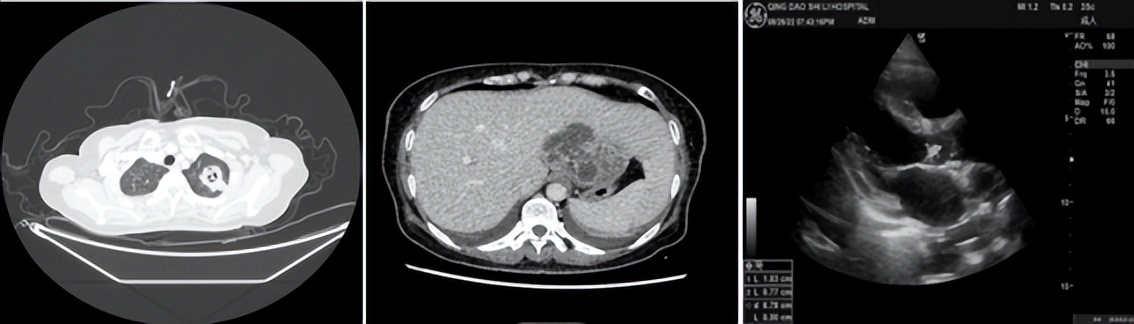

通过转诊绿色通道,患者被第一时间转入我院本部呼吸与危重医学一科。入院后复查影像:胸部左肺团块、斑片灶,考虑肺脓肿;肝左叶团状蜂窝,考虑肝脓肿;心脏超声示主动脉瓣赘生物。

医生立即进行病情分析:患者因长期未能有效控糖,导致身体免疫力低下,而营养丰富的血液却成了细菌培养基,起初一点点的感染逐步加重至严重感染,肝脏内形成接近一个拳头大小的脓腔,肺部病灶均位于胸膜下考虑血源性感染,疑惑的是左上肺病灶呈现“鬼脸征”,同时还伴有感染性心内膜炎及瓣膜赘生物形成。

是否有金黄色葡萄球菌、草绿色链球菌或者隐球菌感染的可能呢?科室立即组织肝胆外科、心外科多学科会诊,专家讨论认为,脓肿治疗的关键在于引流,外院应用广谱抗生素治疗效果不好的原因在于未引流脓肿。为了更快揪出致病菌,急请B超室在超声定位下进行了经皮肝脓肿穿刺引流,不断有砖红色的脓液排出患者体外。穿刺液中白细胞高182279.00×10^6。

有了病原学和药敏的支持,医院立即调整抗生素方案并充分引流,规范管理血糖,患者体温很快降至正常,各项生命体征及指标达临床稳定;仅1周的时间患者肺部病灶、肝脓肿及心脏瓣膜赘生物均明显缩小;引流1月后复查肝脓肿明显缩小,引流液消失,拔除引流管,顺利出院。